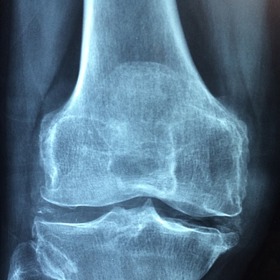

Nemoc přichází pomalu a většina pacientů si prvotních příznaků ani nevšimne. Proto si vysloužila přezdívku ‚tichý zloděj‘ - člověka obírá o kosterní hmotu tak dlouho, dokud na problém neupozorní první zlomenina. V tu chvíli už stačí jen minimální náraz nebo upadnutí. Nejvíc náchylné k frakturám bez zjevných příčin bývají obratle, krčky stehenních kostí nebo předloktí.

Mnoho lidí své problémy mylně pokládá za přirozený projev stárnutí. Zakulacující se záda, snížení výšky postavy i o tři centimetry, bolesti páteře a dlouhých kostí nebo potíže při hlubokém nádechu do břicha nepovažují za podstatné a přehlíží je. Včasná diagnostika přitom výrazně napomáhá zpomalit nebo zastavit progres nemoci.

Jak uvádí Státní zdravotní ústav, osteoporózou trpí sedm až deset procent světové populace, převážně starších ročníků. Vzhledem ke zvyšování průměrné délky života čísla neustále rostou, přesto je léčeno odhadem jen 10 až 20 procent nemocných. Překvapivé zlomeniny pak bývají v pokročilém věku velkým strašákem, zbavují pacienty soběstačnosti a velmi snižují kvalitu života.